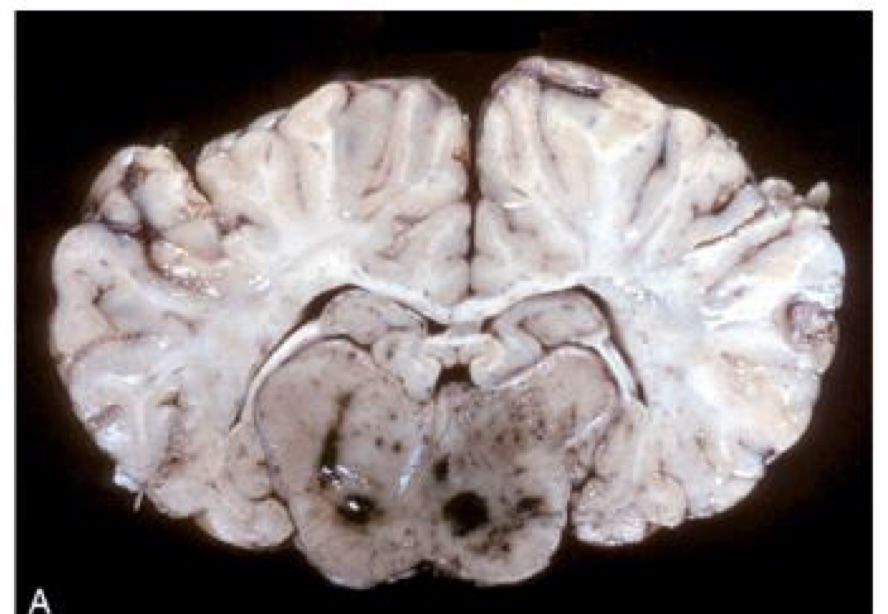

equine encephalomyelitis → thalamus has dark red to black discoloration as a result of congestion and hemorrhage

what is this?

equine encephalomyelitis → red to brown discoloration of the gray matter in the dorsal and ventral horns; focused more heavily on the gray matter